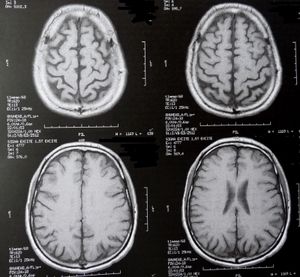

Sie sind hier: Startseite Nachrichten Gesundheit Neurodegeneration bei ALS entschlüsselt Gehirn-Scans: neue Erkenntnisse bei ALS.

Gehirn-Scans: neue Erkenntnisse bei ALS.

Bild: pixelio.de, Dieter Schütz